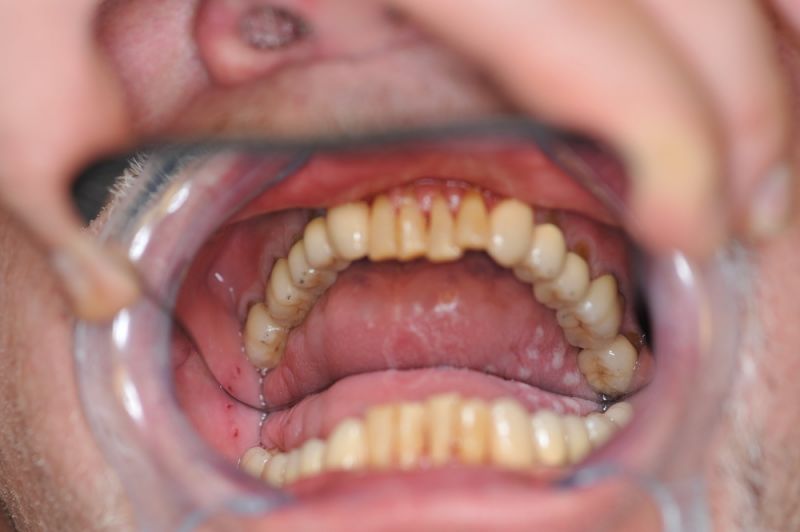

80 jähriger Patient aus Kiel erhält die beiden letzten Rekonstruktionen. Behandlung abgeschlossen

Der Patient erhält die beiden letzten Kronen zur Einstellung der dynamischen Okklusion.

Die funktionstherapeutische Behandlung ist damit abgeschlossen. Der Patient ist vollkommen beschwerdefrei. Beschwerdelevel: "0".

In diesem Fall möglich über die Herstellung von zwei Eckzahnkronen